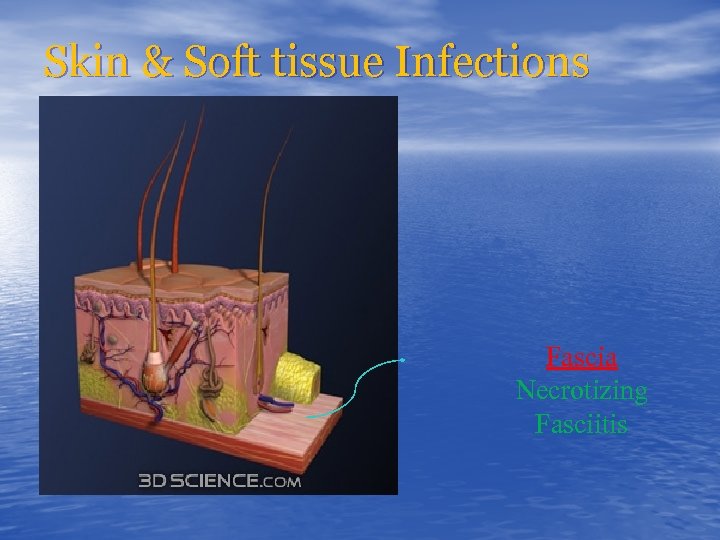

Skin & Soft tissue Infections Fascia Necrotizing Fasciitis

Skin & Soft tissue Infections Fascia Necrotizing Fasciitis